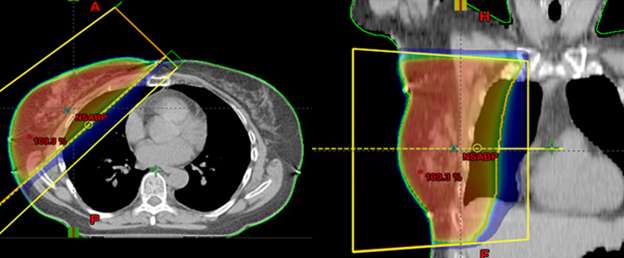

breast cancer

This is in contrast to these examples of standard whole breast radiation where the entire breast is considered the target.